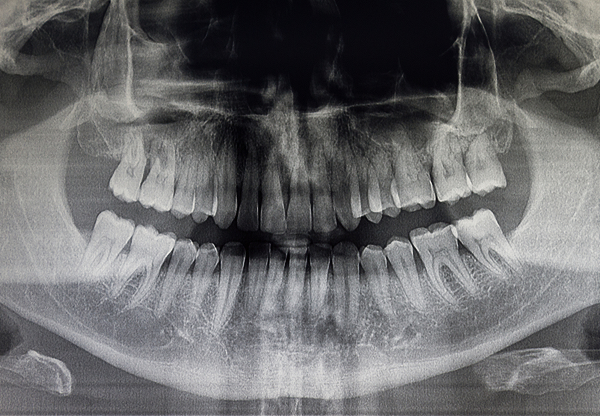

Panoramic X-rays capture your entire mouth, including teeth, jawbone, sinuses, and temporomandibular joints, in a single image.

This Imaging is essential for procedures like orthodontics, dental implants, and wisdom teeth evaluations.

With no intraoral sensors, panoramic X-rays provide a stress-free experience, particularly for patients with a sensitive gag reflex.